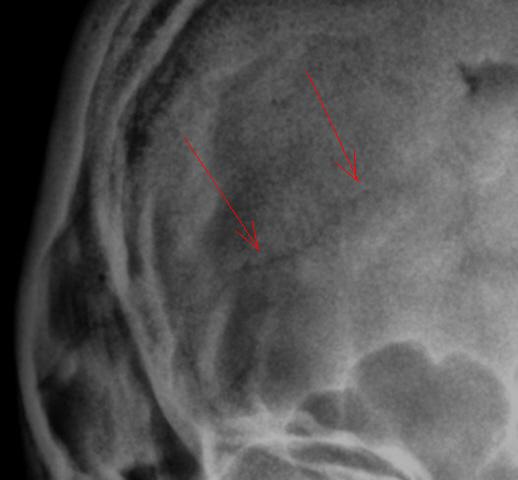

На боковой рентгенограмме нуждаются во внимании, на мой взгляд, помеченные стрелками "линии".

Вызывает сомнения и медиальный край орбиты.